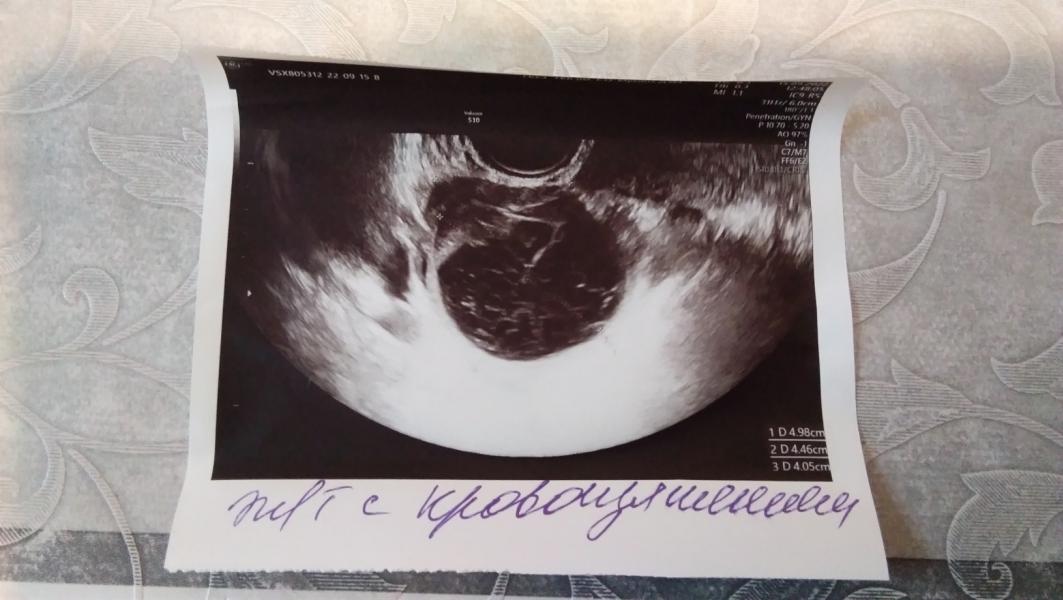

Сходила посмотреть на узи ХОРОШЕЕ ЖЕЛТОЕ ТЕЛО, а тут, на тебе, картина маслом...Узист сказала, что в этом цикле, о беременности можно забыть и, вообще, это " давнишнее желтое тело", а у меня, на минуточку, тератому наблюдают с 2020г, а счас ее не оказалось, но тут ОНО, ДАВНИШНЕЕ. Врач тоже сказала, что с такой хреновиной не может быть беременности, но тем не менее выписала мне Дюфастон по причине: "может быть маленький срок беременности" (дома я прям плакать от счастья начинала, вспоминая ее слова), но, если в этом цикле беременость все же не наступит, отложить придется до декабря. На следующее утро выпила первую таблетку и отправилась в другое место делать узи и...блин, та же фигня только немного меньше уже, да еще нашли мааааленькую кисту возле шейки матки. Долго мне рассказывала, отчего и как появилась, сказала, что овуляции не было( у меня подъем лг гормона в этот цикл был аж на 12 день) и фоликул перерос в кисту желтого тела (!!!!!) ну и, естественно о беременности можно зыбыть, а дюфастон пить до наступления месячных. Вечером искала информацию об этой срани и нарвалась на ссылку на один мамский форум. Там барышни все как одна пишут, что "киста желтого тела это хорошо, это означает беременность, а вот, если нет кисты, а есть одно желтое тело , то все, не беременна; "с ней прогестерон высокий, не будет выкидыша"... У меня мозг просто взорвался от такой противоречивой информации за эти пару дней. И все бы ничего, пить бы мне этот дюфастон и с замиранием сердца ждать задержки, но... У меня начались выделения констинстенции как при овуляции, светло коричневого цвета (простите за такие подробности) и в течение этих двух дней они то есть, то их нет, спину тянет и живот немного. Устала, блин, от такой неопределенности, месячные только 25-26, но такими темпами могут наверное и завтра начаться. Я уже даже на декабрь согласна, пусть только эта зараза уйдет и я "обновленная и чистая" ринусь снова в бой (наверное плохо так думать).

Если это киста именно жёлтого тела, то беременность очень даже возможна. Если это несовулировавший лютеинизировавшийся фолликул, переросший в кисту, то да, тогда беременности не может быть. На УЗИ их бывает сложно отличить. У меня часто не могут. Вы сходите сдайте завтра прогестерон, точно будете знать тогда, была овуляция или нет. У вас как раз его пик должен быть на 7 дпо

@vellamolesya это какая-то ерунда тогда. Беременность возможна с кистой жёлтого тела. Почему 11 ДПО? У вас всплеск ЛГ был на 12 ДЦ, овуляция скорее всего на 13 ДЦ, сегодня 18 сентября, УЗИ у вас от 15ого числа, там был 19 дц. Значит, сегодня 9 ДПО. Нет?